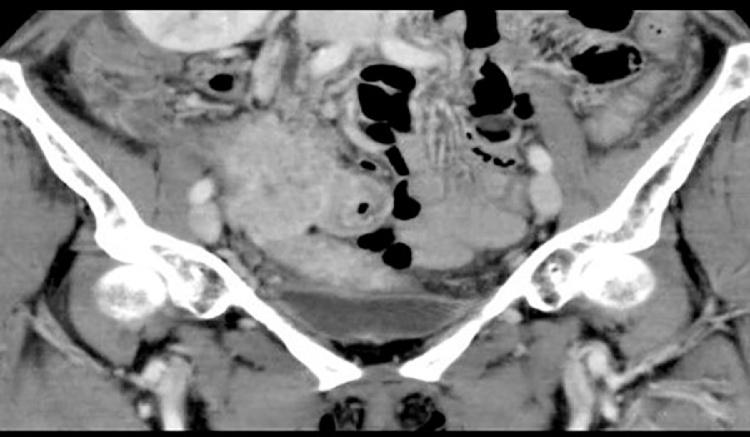

A woman, 60 years old, experienced discomfort in her lower right abdomen. She complained of nausea and anorexia and visited our hospital. Laboratory blood tests, abdominal CT, and abdominal MRI led to a diagnosis of a uterine sarcoma or primary intestinal mass, and she underwent surgery. Her histopathological diagnosis was intraabdominal actinomycosis.

一名60岁女性,右下腹部不适。她主诉恶心和厌食,遂来我院就诊。实验室血液检查、腹部CT和腹部MRI检查后诊断为子宫肉瘤或原发性肠道肿物,随后她接受了手术。其组织病理学诊断为腹腔放线菌病。